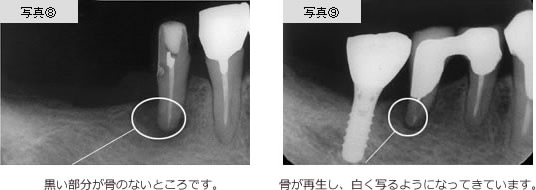

歯根が割れた状態をしばらく放置したために、炎症が起こった症例です。写真5に示すように、くちびる側の骨がほとんどとけてしまい減ってきてしまっています。

1980年代まではこのような症例の場合、骨が十分にないため、インプラント治療ができなかったのですが、1990年代から骨の再生医療技術の開発によって可能になりました。

写真6に示す人工膜、及び自家骨移植技術を用いることによって、骨を再生してインプラントが骨の中に固定できるようになりました。(写真7参照)

写真8に示すような、歯根の周りの骨が喪失している症例では、

元来抜歯でありました。この症例の歯周病に対して、スケーリングなどの治療とともに、この歯の隣の欠損部にインプラントを植立することにより、この歯牙への噛み合わせの力による負担が軽減され、写真9に示すように、歯の周りに骨が再生され抜歯を行うことなく、歯の寿命を延ばすことができます。